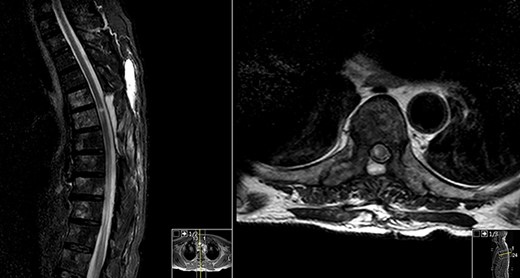

MRI done at this time showed a reduction in the T2 hyperintensity seen in both previous post-op MR scans (Fig. 3).